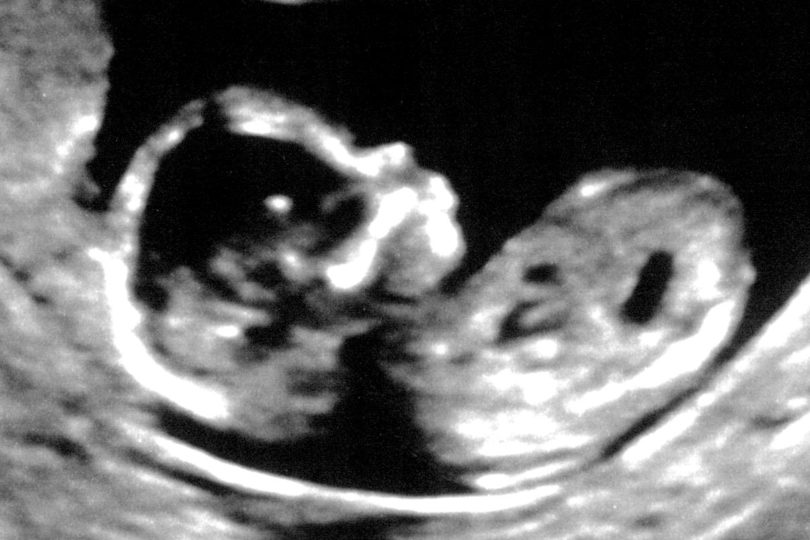

First Ultrasound